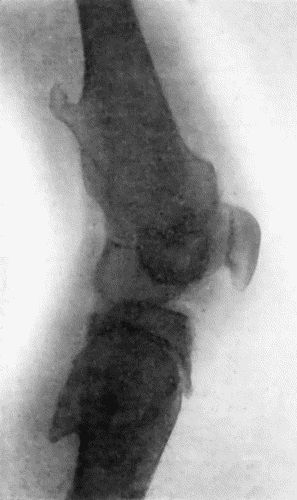

| 151. | Radiogram of Osteo-Sarcoma of Femur | 496 |

| 152. | Radiogram of Chondro-Sarcoma of Humerus | 497 |

| 153. | Epitheliomatus Ulcer of Leg invading Tibia | 499 |